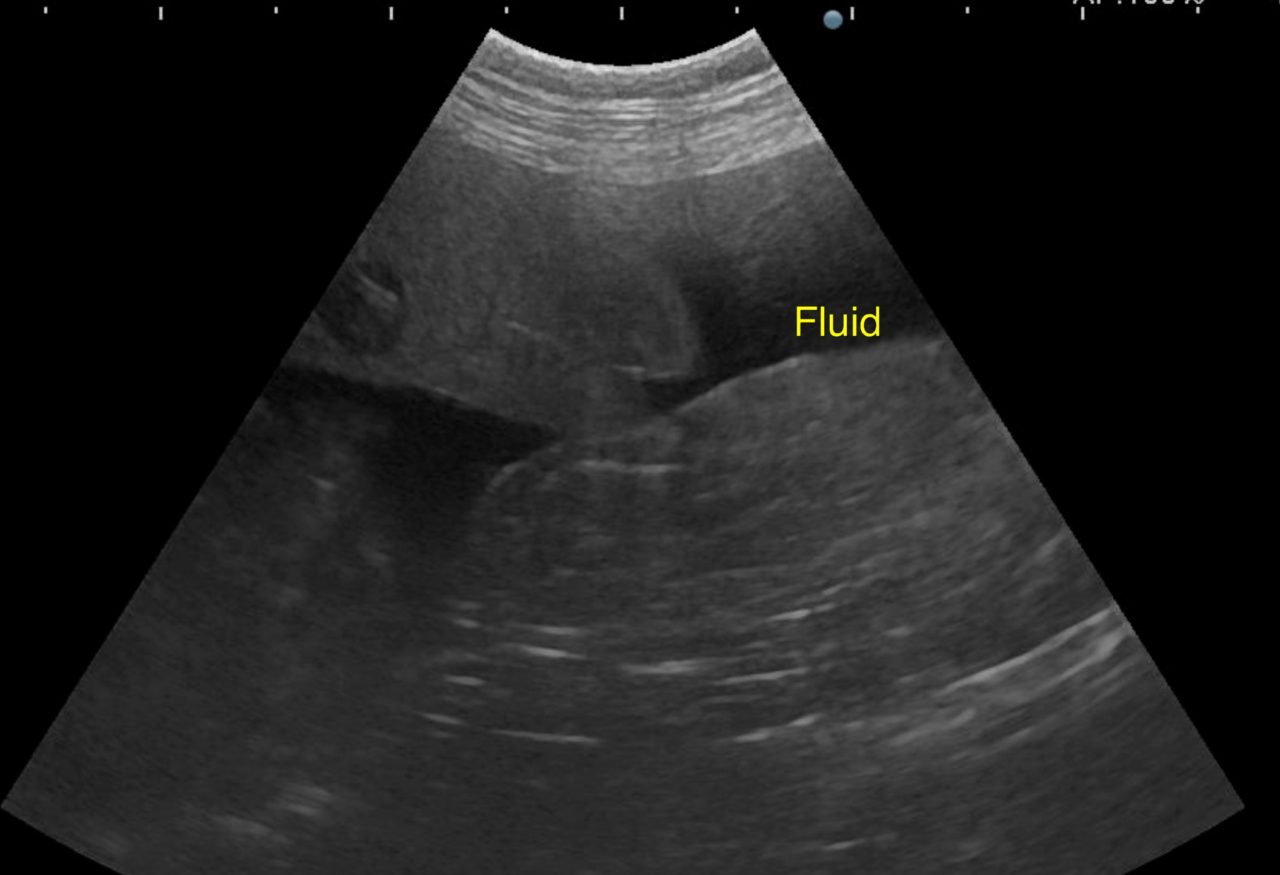

歯茎白い。すぐさま腹部の超音波検査をして”腹腔内液体貯留と腹腔内腫瘤を確認”

この時点で、主治医から電話があり腹腔内からの出血を止めてくれないか?今すぐに患者さんを向かわせるとのこと。

エコーでは脾臓と肝臓にMASSを確認。